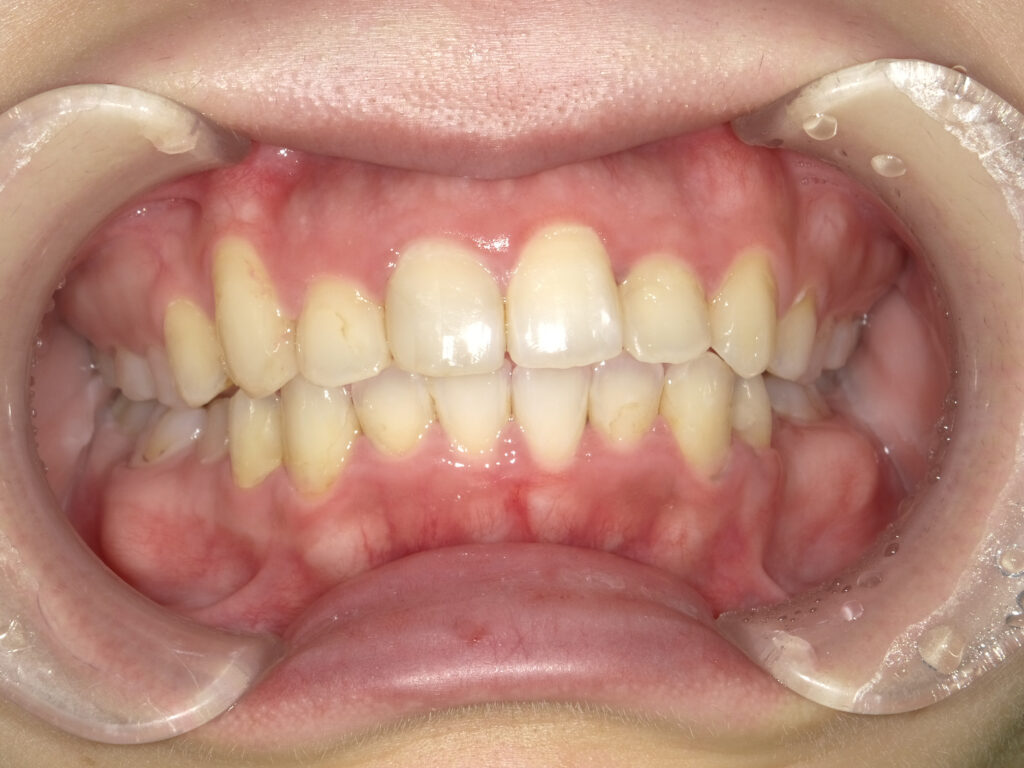

正面

治療後